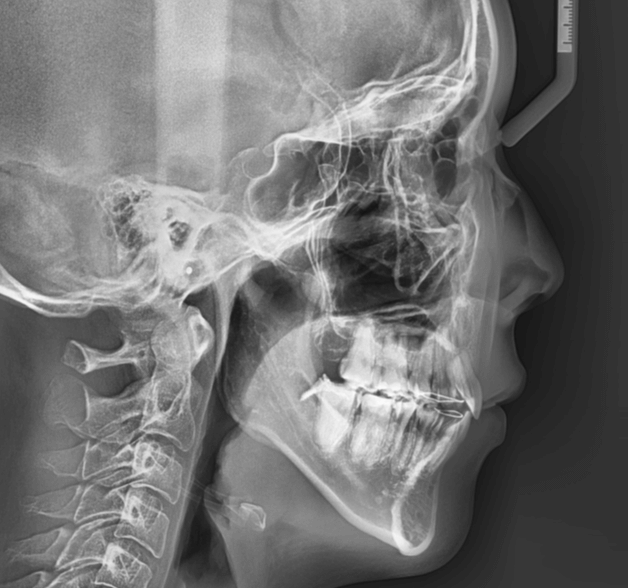

咬み合わせが逆であること(反対咬合)が気になる

| 年齢・性別 | 15歳 女性 |

|---|---|

| 主訴 | 咬み合わせが逆であること(反対咬合)を気にされて来院された女性。見た目や機能面の改善を希望されていました。 |

| 治療期間・回数 | 4年4ヶ月・28回 |

| 費用 | 900,000円 |